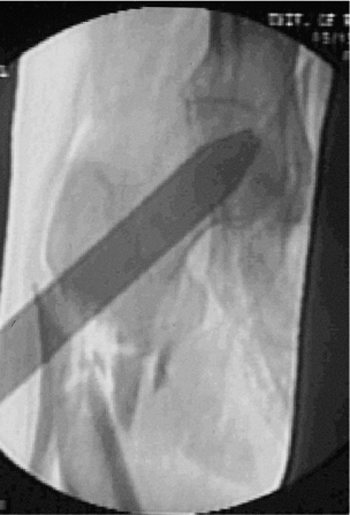

![]() |

Figure 20.16. A,B.

Rotation of proximal drill guide to center guide for correct anteversion of screws into femoral head; drill guide should bisect the femoral head on the true lateral radiographic view. |

Figure 20.17. Lateral fluoroscopic view with bisection of femoral head through use of drill guide for correct screw position.

the femoral head and neck. The proximal targeting guide is aligned with

the c-arm axis by rotating the proximal drill guide

in the transverse plane (Fig. 20.16).

If the proximal targeting device is radiopaque, the guide is

centralized with respect to the femoral head, bisecting the femoral

head in the coronal plane as seen on the true, lateral, c-arm view. The

posterior and anterior portion of the femoral head must be seen in

relation to the proximal drill guide for the surgeon to confirm that

the screws will be contained within the femoral head (Fig. 20.17).